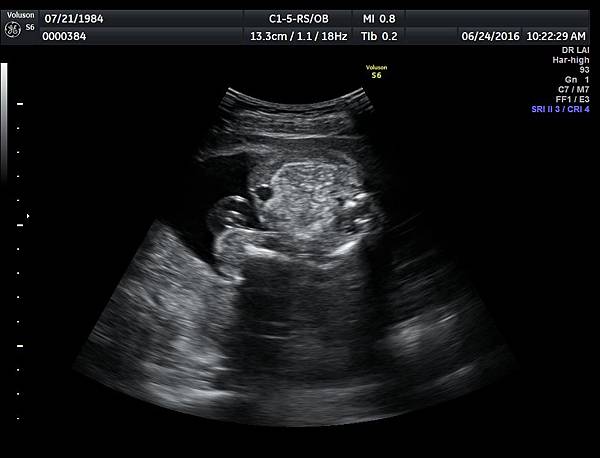

6月24日在我的診所,我幫一位懷孕22週31歲的孕婦看高層次超音波,發現胎兒的腸子很白,形狀也特別的怪( 附圖 1~12 ),我建議她做進一步相關的檢查,包括抽羊水檢查等等。